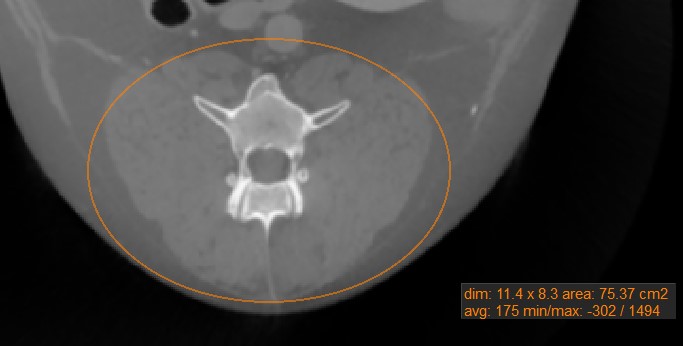

Oval

../_images/image4.jpg

Mark oval areas of the active image slice by using the Oval measurement tool.

Select the Oval tool and assign it to one of the available mouse buttons. Start the measurement by pressing on the active image slice and drag the mouse to obtain an oval shape. Release the mouse when satisfied with the size of the marked area.

All available measurement values are displayed alongside the measurement.

Modify the marked area by moving one of the four points describing the rectangle around the oval shape using the Default tool.

../_images/image311.jpg